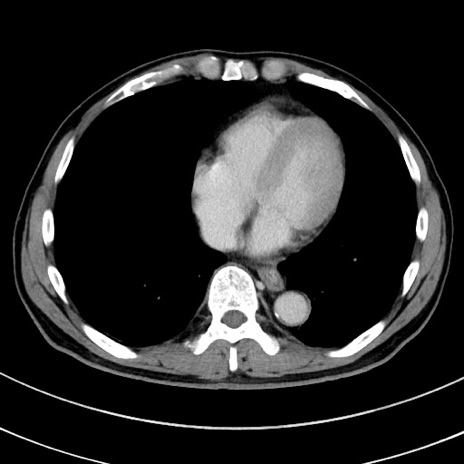

冠状断像

【症例】 60歳代男性

【主訴】 黒色吐物

【現病歴】 4日前から嘔気自覚、2日前の朝食後にも嘔気あり、自分で手で嘔吐反射起こし嘔吐したところ血が混ざっていたため受診。

【既往歴】 5年前汎発性腹膜炎を伴う急性虫垂炎で手術、高血圧、前立腺肥大症、高脂血症

【身体所見】 腹部正中に手術癩痕あり 腹部平坦・軟圧痛なし膨満感あり

【データ】WBC 8400、CRP 4.54